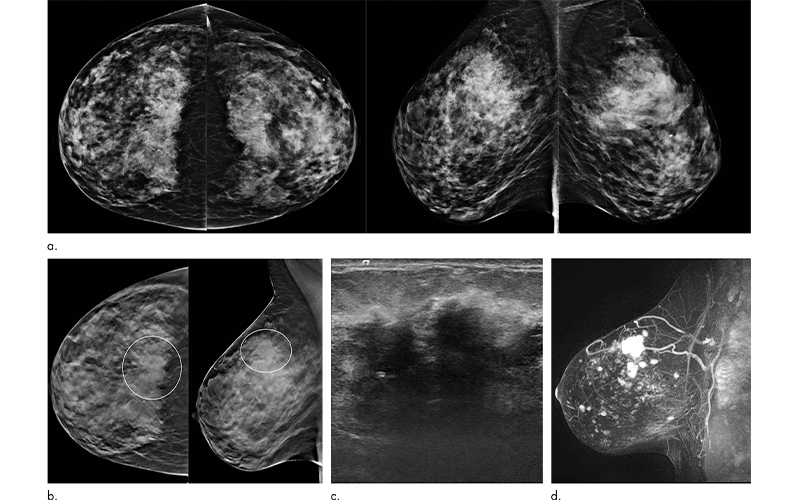

A new study in Radiology has found that the advantages of digital breast tomosynthesis (DBT) over digital mammography (DM), including increased cancer detection and fewer false positive findings, are maintained over multiple years and rounds of screening.

“As a radiologist, tomosynthesis allows viewing of the breast in multiple layers or slices,” said study lead author Emily F. Conant, MD, professor and chief of breast imaging in the Department of Radiology, Perelman School of Medicine at the University of Pennsylvania in Philadelphia. “This ability to scroll through slices of otherwise overlapping breast tissue helps us not only detect more cancers but also better characterize benign or normal areas of the breast.”

Dr. Conant attributed the improved outcomes achieved with tomosynthesis to better visualization of both benign and malignant lesions and a reduction in tissue superimposition.

“With tomosynthesis you can remove some of the overlapping or obscuring breast tissue so that both normal and abnormal findings are better seen,” she said. “That provides both improved cancer detection and decreased false positives.”